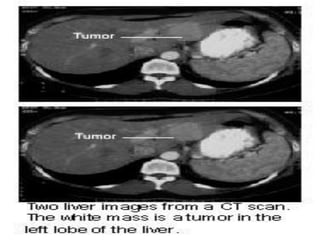

2.3.2.C¸c xÐt nghiÖm th¨m dß h×nh th¸i

■Siªu ©m bông:

+Khèi u: ↓ ©m, ↑ ©m, hçn hîp ©m, quÇng halo

+X©m lÊn TM cöa, TM trªn gan

+D·n ®êng mËt trong gan ë phÝa trªn khèi u

■CT bông cã tiªm c¶n quang

+Tríc khi tiªm c¶n quang: khèi u ↓tû träng, canxi

ho¸ t¹i khèi u, x©m lÊn h¹ch, mµng bông

+Sau tiªm c¶n quang: khèi u ↑tû träng (t¨ng m¹ch

m¸u), x©m lÊn TM cöa vµ TM trªn gan